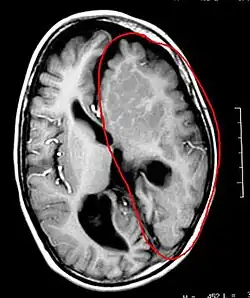

L'hémisphérectomie est une opération chirurgicale où un hémisphère cérébral (une moitié du cerveau) est enlevé ou déconnecté de l'autre hémisphère. Cette opération est utilisée pour traiter le syndrome de Rasmussen, et les enfants qui ont eu des accidents vasculaires cérébraux handicapants ou qui ont des crises d'épilepsie extrêmement fréquentes.